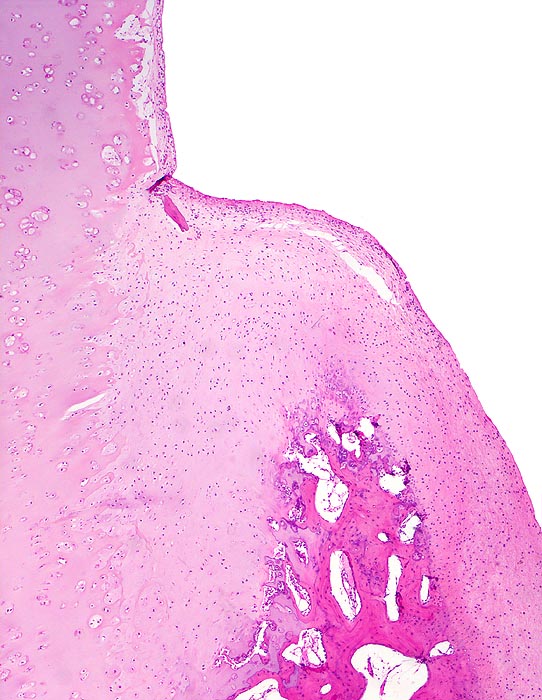

Coxarthrose: Randosteophyt

Übergang des residuellen hyalinen Gelenkknorpels in den Randosteophyten bedeckt mit neugebildetem Knorpel. Letzterer besteht nicht aus vollwertigem, Kollagen II-haltigem Knorpel, sondern aus Typ I und II-Kollagen. Daraus resultiert eine verminderte Belastbarkeit dieser neuen Gelenkfläche.

74-jährige leicht adipöse Patientin mit Anlaufschmerz, belastungsabhängigem Schmerz und zunehmender Versteifung im Hüftgelenk. Im Röntgenbild des Hüftgelenks zeigen sich eine Gelenkspaltverschmälerung, subchondrale Osteolysen, Usuren und randständige Osteophyten.